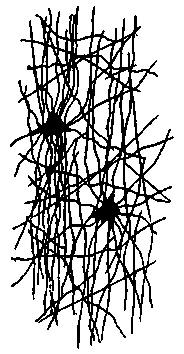

| 15. | Neuroglia cells of the fascia dentata, in the new-born rabbit | 121 |

| 16. | Neuroglia cell from the subcortical layer of the cerebrum from which two processes go to a blood vessel | 122 |

| 17. | Neuroglia cells from the spinal cord | 122 |